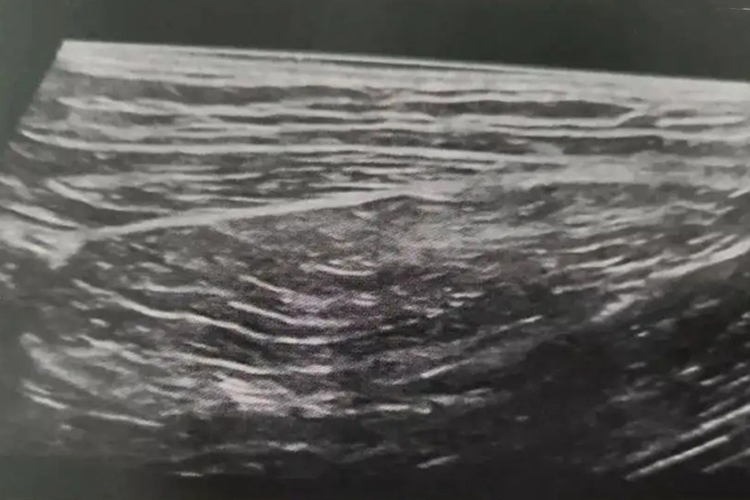

脂肪瘤通常位置表浅,为纺锤形、边界清晰的低回声,呈现特征性的高回声条带或“羽状”结构;对于位置表浅的脂肪瘤,可以显示其包膜,对于位置深在、呈浸润性生长的脂肪瘤,超声同样可以识别出其不清晰的边界。